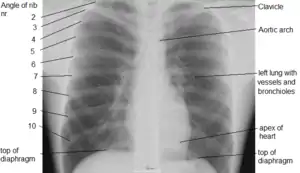

Рентгенограмма органов грудной полости